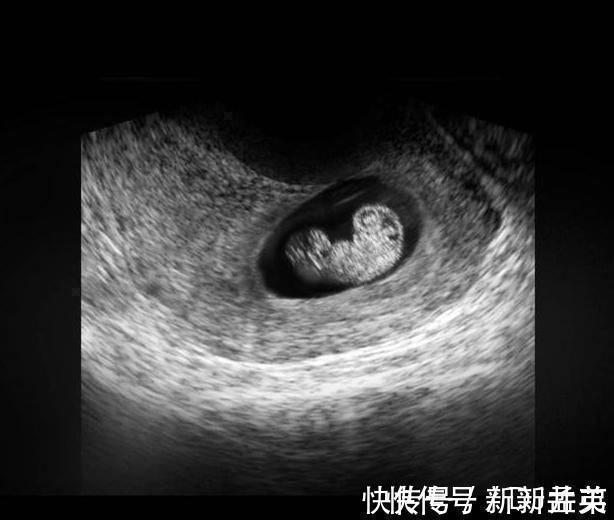

上图可见子宫中的囊状结构,胎儿由两层的组织构成胚胎,所有的器官和组织都是有这些组织发育而成,胚胎羊膜囊的空腔中,开始有羊水积聚,为将来包裹和保护胎儿做准备。